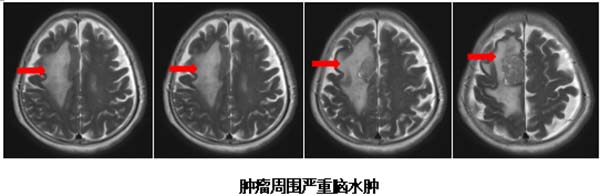

检查结果揭示了她病情急转直下的原因:头部MRI显示右侧额叶运动前区皮层转移灶,伴有明显脑水肿,严重压迫运动功能区。更复杂的是,胸部CT发现了右肺占位病变。高龄、病情进展迅速、肺部原发病变,使这个病例充满挑战。